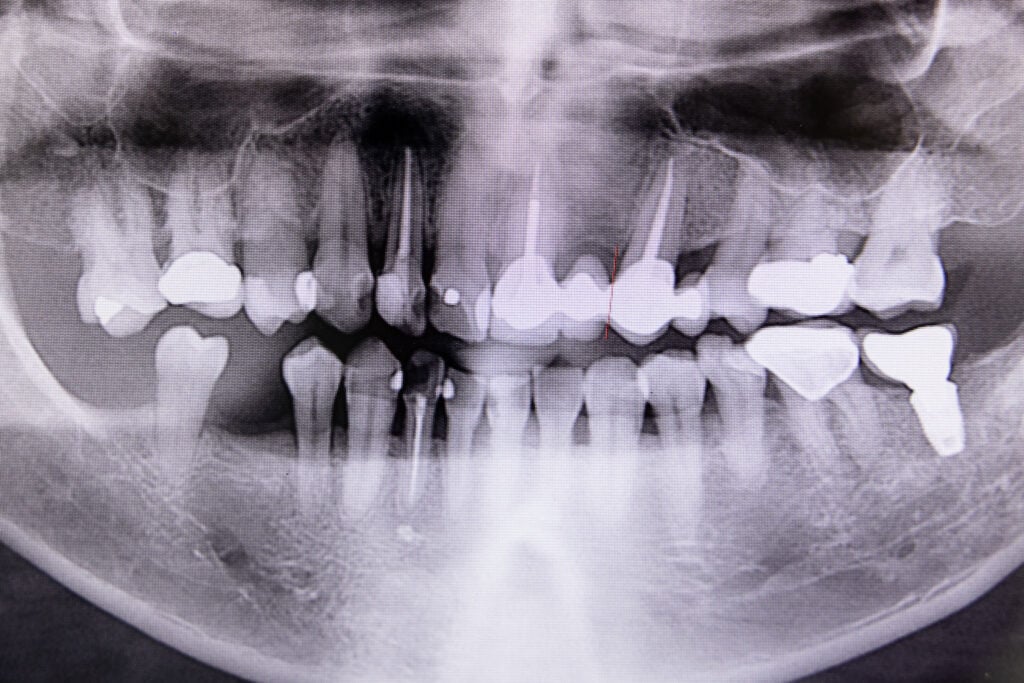

Root canal treatment treats infection in the centre of a tooth caused by bacteria that live in the mouth and invade the tooth. Infections can occur due to tooth decay, leaking fillings, or tooth damage.

The duration of your treatment depends on the specific tooth; front teeth usually have a single, straightforward root canal, while back molars can have up to four complex, curved canals.

This exam will include your teeth and gum health, structural integrity, bite function, cosmetic aspects, and any X-rays needed.